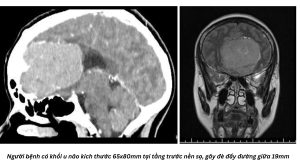

Các bác sĩ tại Bệnh viện Đa khoa Thái Bình vừa trải qua một cuộc